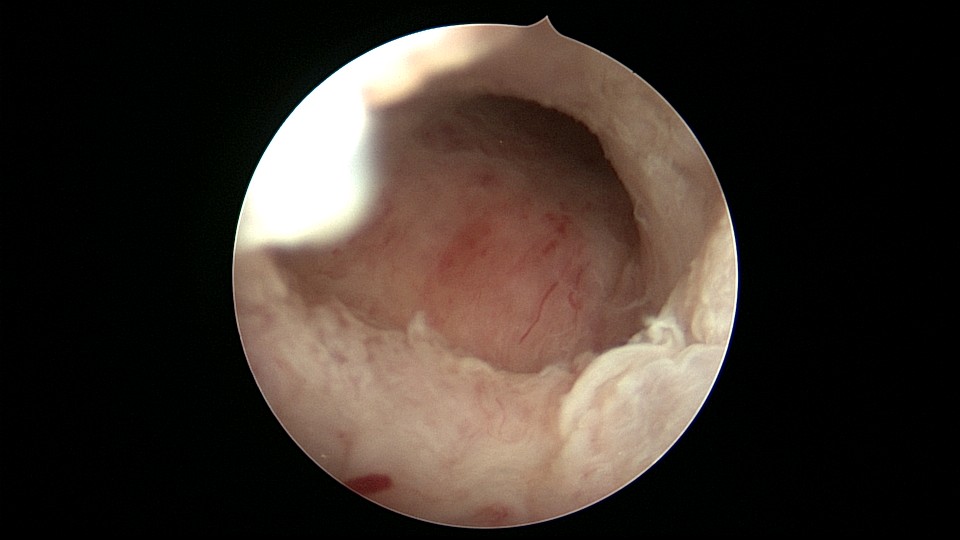

患者68岁,G3P1,顺产1次,安环42年,绝经20年,外院取环失败。子宫后位,宫颈及子宫萎缩,距宫颈内口1cm以上宫颈管封闭致密粘连,B超监护下异物钳分离粘连,打开进入宫腔的通道,艰难扩宫至6号扩宫棒,见O型环与两侧宫壁崁顿,异物钳无法取出,取环钩将环拉至宫颈外口,中弯钳牵拉,完整取出节育环,环变形,很艰难的取环经历。